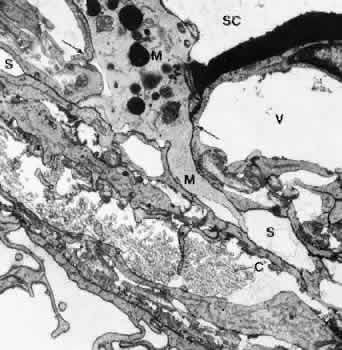

The endothelial lining of the canal consists of a complete monolayer of flat endothelial cells that, like other vascular endothelial cells, stain for factor VIII and plasminogen.27 Unlike other vascular endothelium, the endothelial cells of Schlemm's canal do not rest on a complete basement membrane. A basement membrane is formed initially during embryonic development, but it gradually disappears as aqueous circulation starts.28,29 In its final form Schlemm's canal is more comparable with a lymphatic than a blood vessel. Lymphatic vessels do not usually possess basement membranes. Their endothelial lining is perfused from outward to inward and often connected with elongated cytoplasmic processes of adjacent pericytes. As in lymphatics, the endothelial cells of the inner wall of Schlemm's canal also develop cytoplasmic processes that interdigitate with similar processes of underlying cells of a second row underneath the canal endothelium (Fig. 15). The subendothelial cell layer is not complete and consists of elongated, star-like cells oriented predominantly in a radial anteroposteriordirection. In contrast, the endothelial cells ofSchlemm's canal, measuring about 160 μm in length and covering an area of 408 μm2 run mostly in an equatorial direction.30 The cellular and fibrillar connections with the cribriform layer may stabilize the inner wall during IOP variations and changes in the perfusion rate. The double-layered structure of the inner wall is often seen to be elevated and protrudes into the lumen of the canal when IOP is particularly high at the time of tissue fixation. If IOP is low, the two cell layers are pressed together from the luminal side, thus presumably preventing a reflux of blood into the TM and anterior chamber.31,32

Fig. 15. Electron micrograph of sagittal section of the inner wall of Schlemm's canal (SC) after perfusion with cationized ferritin (CF) (cynomolgus monkey, × 21,000). Note the labeling of cell membranes with cationized ferritin and the enlarged paracellular route (P).E, endothelial cells of the canal; GV, giant vacuole; S, subendothelial cells of cribriform layer; V, small vacuole. (Epstein DL, Rohen JW: Morphology of the trabecular meshwork and inner wallendothelium after cationized ferritin per-fusion in the monkey eye. InvestOphthalmol Vis Sci 32:160, 1991)